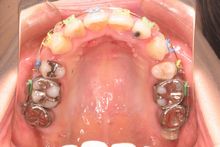

初診時上顎

初診時の口腔内写真です。上顎の中切歯に翼状捻転が認められます。また、下顎にも叢生が認められます。スペースの不足量は上顎5mm、下顎10mmでした。

上顎両側の第一小臼歯と下顎両側の第二小臼歯を抜歯(合計4本)し、効果的に上顎前歯の後退をはかるため上顎臼歯部に固定源のための歯科矯正用アンカースクリュー(ミニインプラント)を植立することにしました。

治療開始12ヵ月後上顎

治療開始12ヶ月後の口腔内写真です。下顎の叢生はほぼなくなっています。矯正用アンカースクリューを固定源として上顎前歯部を後方に牽引しているところです。カラーモジュールを使用しています。本症例では青、黄、緑ですが、赤、金、銀、紫など20色程度あります。ご希望の患者様はお申し付けください(無料です)。